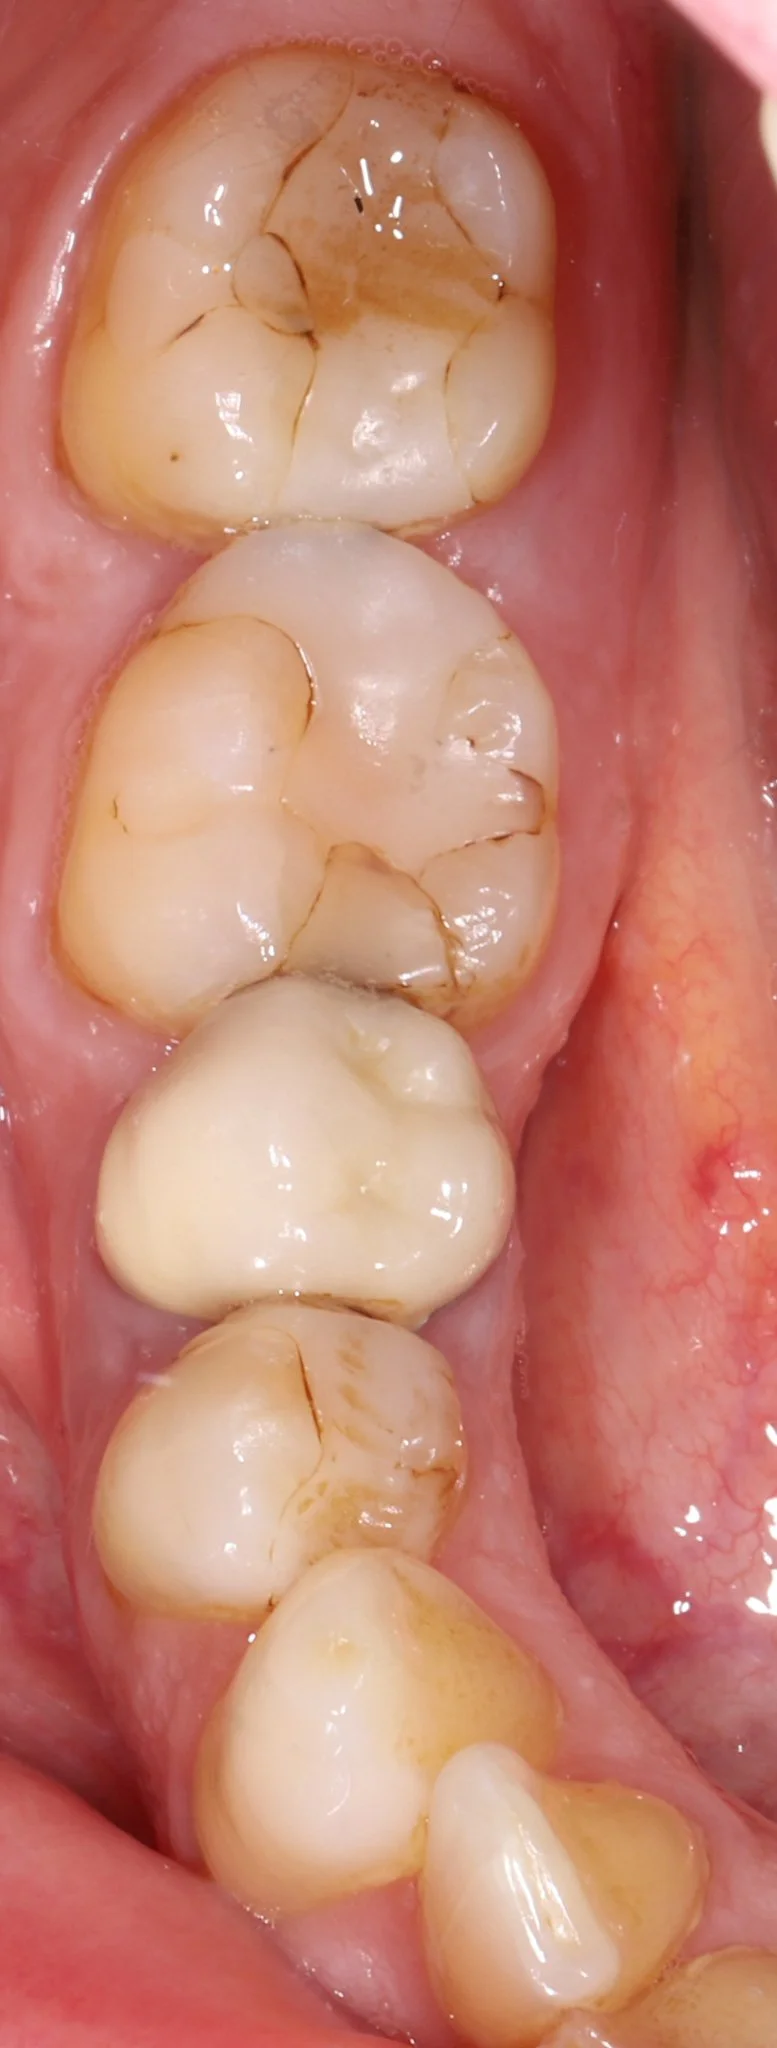

Close-up of human molars and premolars with visible signs of staining and early decay in the back teeth.

Before: Decay, food traps, leaking old dentistry, nothing fits or blends in

Close-up of four white molar teeth inside a person's mouth.

After: Proper fit, gum tissue health, natural restorations